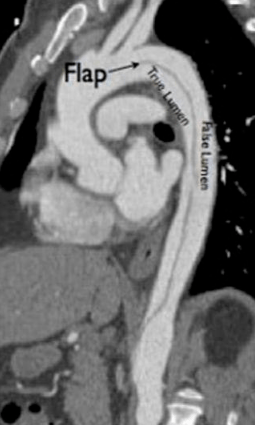

主动脉夹层近期呈高发趋势 这4类人群要警惕他们就接诊了13位主动脉夹层患者,而全院范围内收治的A型、B型及复杂型主动脉夹层患者数量更是远超这个数字。主动脉夹层到底是一种什么病?为什么它会在近期“扎堆”出现?主动脉夹层是什么病?主动脉是从心脏延伸出来的一根给全身供血的大动脉,由内膜、中膜和外膜三层组成...

阳光融和医院成功救治一例A型主动脉夹层患者其特点是主动脉内膜撕裂后,血液进入主动脉壁内形成夹层,随时可能引发主动脉破裂、心包填塞、急性心肌梗死等致命并发症。 更严峻的是,检查结果显示主动脉夹层累及:主动脉根部、升主动脉、降主动脉至双侧髂血管,右冠状动脉开口、头臂干、左锁骨下动脉、腹腔干等形成夹层及壁...

警惕!主动脉夹层:胸背痛背后的隐秘致命威胁前言: “医生,我的背痛得厉害!”在急诊室里,这样的情景并不罕见。然而,对于急诊医生而言,这种症状背后可能隐藏着多种疾病,其中最需要警惕的就是主动脉夹层。这是一种与时间赛跑的紧急情况,往往是高血压患者的无声杀手。 什么是主动脉夹层? 主动脉是人体的主要供血通道,负责将...

主动脉夹层:隐藏在胸背痛背后的致命杀手前言: “医生,我背痛得厉害!”急诊科里,类似这样的患者并不少见。但对于一名急诊医生来说,这背后可能隐藏着无数种疾病,其中最需要警惕的,就是主动脉夹层。这种“时间就是生命”的急症,常常是高血压患者的无声杀手。 什么是主动脉夹层? 主动脉是人体的&ld...